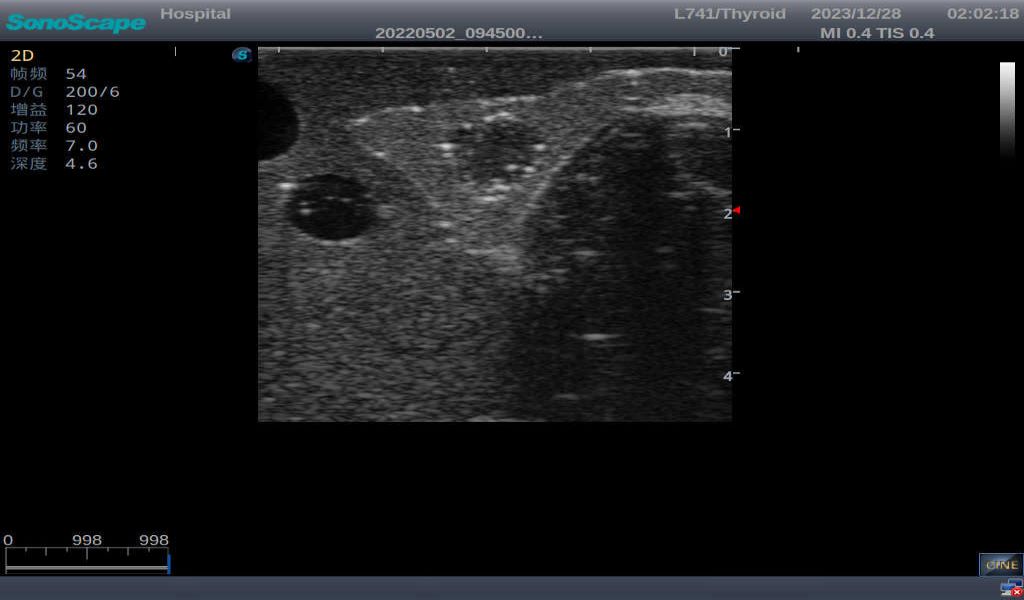

3)       It comes with four (4) thyroid modules and can show five (5) ultrasonic images: normal thyroid, thyroid adenoma, thyroid cancer, nodular goiter, thyroid cyst

Normal thyroid with homogeneous parenchymal echo and well-defined capsule

Thyroid adenoma with well-defined border and smooth uniform halo

Thyroid cancer with irregular mass, unclear border, uneven internal echo or calcification strong echoes

Nodular goiter with irregular border and varying sizes of low echo, isoechoic, or high echo nodules

Thyroid cyst, which fluid area, dark and echo-free area can be seen